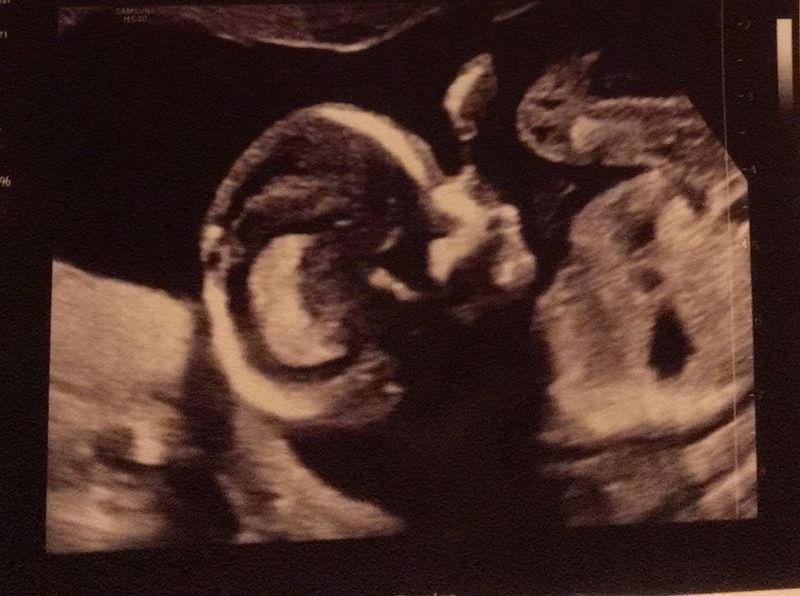

De 20 weken echo

Het was woensdag 30 december. Deze ochtend stond de 20 weken echo gepland. Zelf heb ik een afwijking aan de urineleiders en dat is reden om een GUO te krijgen in het ziekenhuis. Ik was hier 19.5 weken zwanger en al deze weken klonk er een stemmetje in mijn hoofd die zei: “Wees nog niet te blij Maartje. Koop nog maar niks. Eerst de 20 weken echo afwachten, dan kijken we wel verder. Eerst zien, dan geloven”. De gynaecoloog die de echo uitvoerde was dezelfde als bij Jake bijna 8 jaar geleden. Dat was fijn, een bekend gezicht. Ik mocht gelijk gaan liggen. Phoe, wat was ik zenuwachtig. Ze praatte gelukkig veel over wat ze zag en ze was heel enthousiast. Een knap kind vond ze hem. Hij was heerlijk aan het spartelen en trapte zo af en toe tegen de doppler aan. Doordat hij zo druk was, was het lastig kijken naar zijn hartje. Ze besloot eerst alvast even de gegevens in de computer te zetten over alle goede dingen die ze had gezien. Wij zochten er nog niks achter en waren blij dat alles er goed uit zag. Achteraf denk ik dat ze misschien tijd aan het rekken was om te bedenken wat ze wellicht al vaag had gezien. Ze ging verder kijken naar het hartje. Voor een leek zag het er prima uit. Twee kamers, twee boezems. De bloeddoorstroming werd gecontroleerd. De gynaecoloog bleef maar kijken en kijken. Dat leek wel eeuwen te duren.

Missing alt text

Slecht nieuws

Op een gegeven moment kregen we het wel een beetje benauwd en hoopte ik dat ze heel snel zou zeggen: “Ook het hartje is helemaal goed gekeurd”. Toen kwamen de woorden die ervoor zorgde dat de grond onder onze voeten vandaan geslagen werd. Ik lag daar op dat bed en mijn lijf werd zwaar, heel zwaar. Ik voelde paniek in me opkomen. “Sorry”, zei ze, “maar ik moet jullie doorsturen voor verder onderzoek van zijn hartje. Er is iets niet te zien, wat ik wel graag zou willen zien. Ik hoop dat ik het mis heb, maar het moet verder beoordeeld worden”. Wat er dan door je heen gaat, is met geen woorden te beschrijven. Was ik daarom met alles zo terughoudend? Wist mijn moedergevoel al dat er iets mis was? De gynaecoloog kon er verder vrij weinig over zeggen, alleen dat ze het vermoeden had op een gaatje tussen de kamers en een vernauwde longslagader. Er werd direct gebeld naar het Erasmus ziekenhuis voor een spoedecho. Vanwege Oud en Nieuw en Corona was er helaas niet eerder plek dan maandag 4 januari. Kak, hoe komen we deze dagen door? Hoe moeten we Oud en Nieuw vieren met deze onzekerheid? Verslagen verlieten we het ziekenhuis. Op naar de jongens die met onze oppas thuis waren. De dagen erna probeerden we zo goed als het lukte positief door te komen. Mijn zorgen waren groot. Het zat continu in mijn hoofd en ik was ontzettend bang.